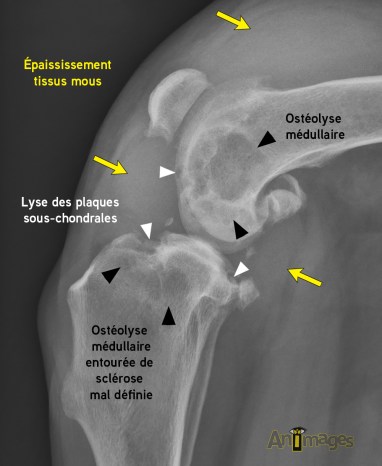

Les radiographies montraient tout d’abord un épaississement très marqué des tissus mous articulaires du grasset effaçant complètement les gras infrapatellaires et faisant protrusion de façon circonférentielle au grasset pour s’étendre proximalement à la rotule et latéralement à la fibula proximale. Plusieurs foyers d’ostéolyse à contour plus ou moins mal défini sont aussi visibles en région métaphysaire fémorale distale ainsi qu’au plateau tibial et aux fabelles. Cette ostéolyse implique non seulement la cavité médullaire, mais également les cortex et plaques sous-chondrales, particulières en portions crâniale et caudale du plateau tibial ainsi qu’à la trochlée fémorale. Une prolifération osseuse médullaire mal définie de plus faible amplitude est visible au pourtour des foyers lytiques.

De plus, une prolifération périarticulaire, cette fois mieux définie, est également présente au pourtour des composantes articulaires. Deux foyers minéraux assez bien définis sont aussi visibles dans les tissus mous intra-articulaires du grasset. Finalement, on note une amyotrophie marquée des muscles de la cuisse.

Avant d’établir une liste de diagnostics différentiels plausibles et de déterminer les étapes diagnostiques ou thérapeutiques pertinentes pour ce chien, on doit d’abord caractériser le comportement de l’ensemble de ces lésions. Tout d’abord, la nature irrégulière et mal définie de l’ostéolyse qui implique également le cortex et les plaques sous-chondrale est celle d’un processus agressif. La réaction osseuse médullaire mal définie est aussi de nature active. Une composante de prolifération périarticulaire mieux définie et compatible avec de l’ostéophytose est aussi présente et signale donc une composante d’ostéoarthrose qui semble toutefois indépendante des lésions médullaires et corticales au caractère plus agressif et plus actif.